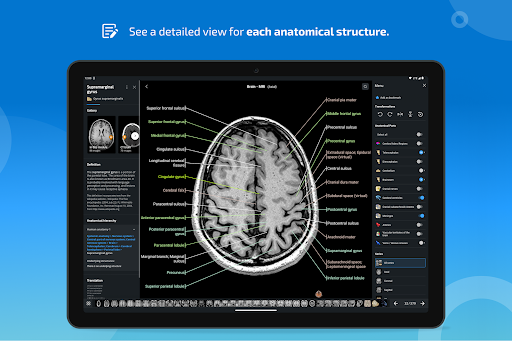

IMAIOS e-Anatomy es un atlas de anatomía humana para médicos, radiólogos, estudiantes de medicina y técnicos en radiología. Echa un vistazo a más de 26 000 imágenes médicas y anatómicas de forma gratuita antes de suscribirte a nuestro detallado atlas de anatomía humana.

e-Anatomy tiene más de 26 000 imágenes que contienen series de imágenes en vistas axiales, coronales y sagitales, así como radiografías, angiografías, imágenes de disección, gráficos anatómicos e ilustraciones. Todas las imágenes médicas fueron etiquetadas cuidadosamente, más de 967 000 etiquetas disponibles en 12 idiomas, incluida la Terminologia Anatomica latina.

- Toque las etiquetas para mostrar las estructuras anatómicas

- Localice fácilmente las estructuras anatómicas gracias a la búsqueda de índice

*Vista detallada mejorada de partes anatómicas para una identificación más fácil en imágenes del módulo actual y otros.